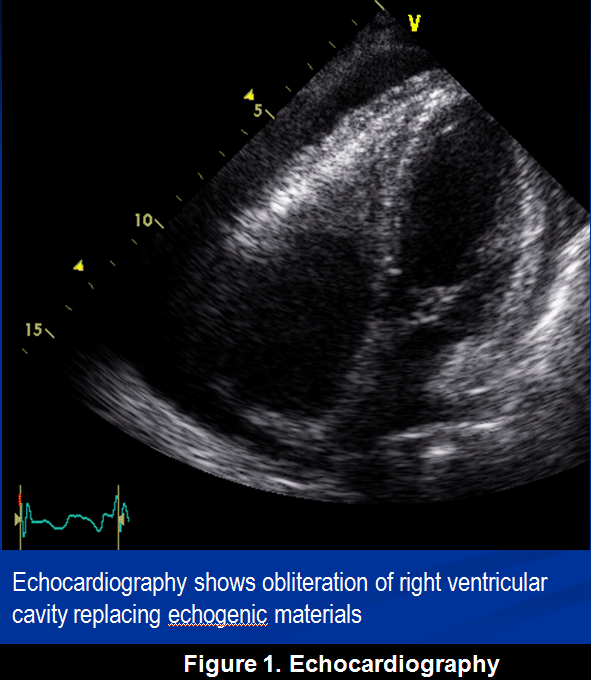

abnormality in echocardiography 22/M

Mi Jung Park, Gyeongsang National University School of Medicine, Gyeongsang National University Hospital